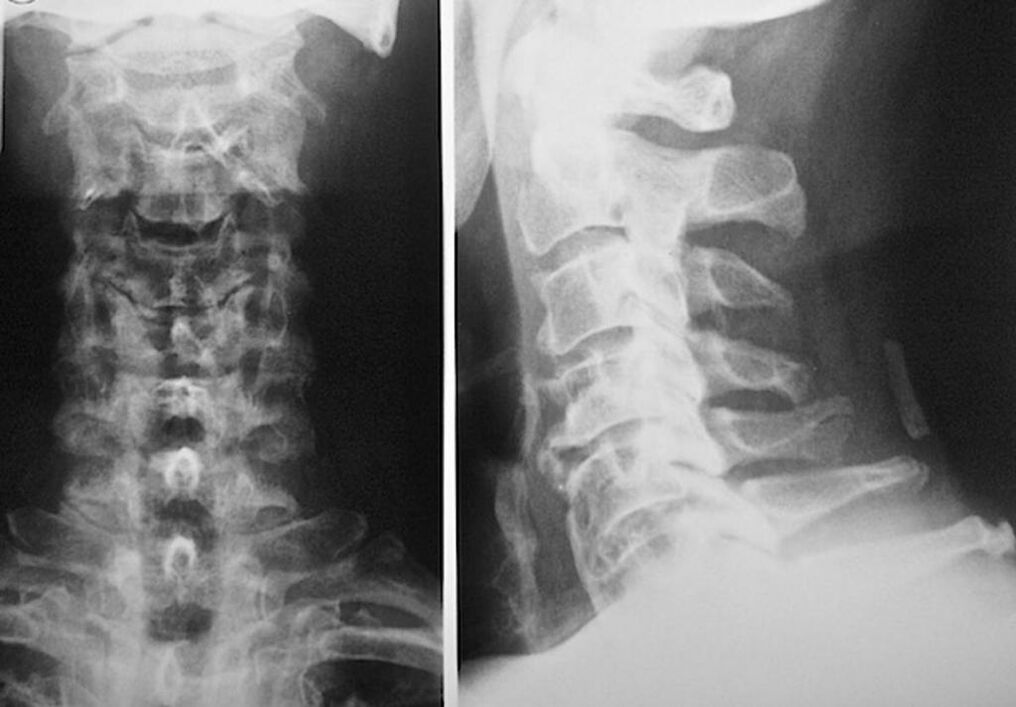

Diagnose Osteochondrose: An welchen Arzt wenden Sie sich?

Um eine Behandlung für Osteochondrose der Halswirbel zu diagnostizieren und zu verschreiben, müssen Sie sich für eine Konsultation bei einem Neuropathologen und einem Orthopäden anmelden. Ein Neurologe kann Heilmittel für die Manifestationen der Krankheit verschreiben, die den Zustand der Nervenenden beeinflussen. Dies ist sinnvoll, wenn die Krankheit von einem Wurzelsyndrom begleitet wird. Der Orthopäde wird den Zustand der Wirbelsäule beurteilen und das Vorhandensein zusätzlicher Krankheiten diagnostizieren: Skoliose, Lordose usw.

Zur Diagnose und genauen Beurteilung des Zustands der Bandscheiben werden folgende Untersuchungsmethoden verwendet:

- Knochenscan.

- Computertomographie

- Magnettomographie.

- Sonographie der Halsgefäße.

Jeder von ihnen ist absolut gesundheitlich unbedenklich und birgt keine Gefahr einer übermäßigen Exposition. Die Diagnose einer Osteochondrose der Halswirbel, deren Behandlung für den Rest des Lebens durchgeführt wird, kann nach einer einfachen visuellen Untersuchung gestellt werden. Jeder Orthopäde kann dies problemlos tun. Eine Ausnahme ist das erste Stadium der Krankheit, wenn keine sichtbaren Pathologien der Halsregion festgestellt werden.